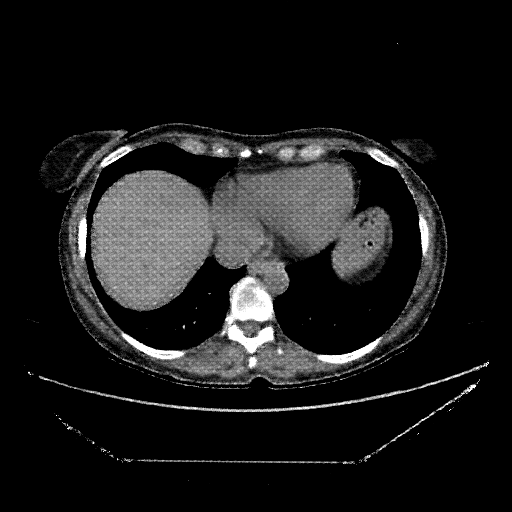

Image Grid

4Γ—3 grid: Rows show different image types (Original NATIVE, Reconstructed NATIVE, Original VENOUS, Generated VENOUS), Columns show windowing techniques (No Window, Lung Window, Mediastinum Window)

Original NATIVE CT scan (input)

Full window (WL 1023.5, WW 4095 β†’ Low βˆ’1024, High +3071)

Generated VENOUS CT scan (A→B translation)

Mediastinum window (WL 40, WW 400 β†’ Low βˆ’160, High +240)